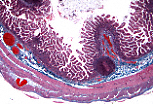

该回肠壁切片中可见黏膜皱襞。

皱襞上突出的指状突起即为肠绒毛。 |

肠绒毛由中央结缔组织轴心和表面覆盖的肠上皮构成。绒毛之间可见 利贝昆氏腺(肠腺) 的开口。 |

衬贴利贝昆氏腺的上皮与覆盖肠绒毛的肠上皮结构相似。 |

肠上皮通过基膜与下方的结缔组织相连。细胞的基底面贴附于基膜,游离面朝向肠腔。细胞核呈单层排列于高柱状细胞的下1/3处。这一形态学特征表明肠上皮属于单层柱状被覆上皮。 |

肠上皮细胞的形态特征与其功能特化相适应。

吸收细胞为高柱状细胞,卵圆形细胞核位于基底部,游离面有一粉红色区域即纹状缘,其下方有一条嗜酸性红线。透射电镜显示,纹状缘由微绒毛构成,为吸收细胞提供了巨大的游离面以吸收营养物质;而嗜酸性红线对应终末网——这是一种细胞质区域,微绒毛内的肌动蛋白微丝在此锚定于中间丝。 |

肠上皮中的 杯状细胞 具有三角形的深染基核,游离面细胞质因黏原颗粒堆积而透亮、膨大。黏原和黏液不被三色染色法着色。 |